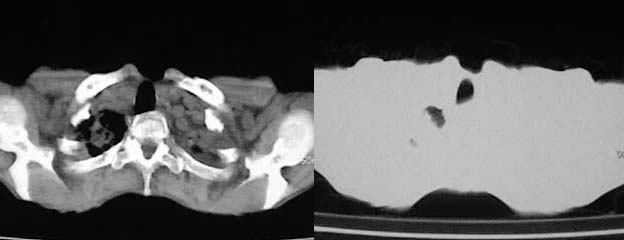

以下是引用zjzjr在2008-5-2 14:39:00的发言:[br]支持双侧继发型肺结核,左侧胸膜肥厚,慢性支气管炎伴间质纤维化.

以下是引用有风的日子在2008-5-2 12:13:00的发言:[br][emb10][br][br]肺ca?有病理支持吗?[br][br]我看更象是肺tb并支扩、间质性肺炎。最好拿个病理结果来,不然这点影像资料诊断肺ca是难以服人的![br][br]至于主动脉瘤的诊断问题,国外认为≥4.0cm就可诊断了,国内对此诊断标准更为严格。患者升主动脉明显增粗,即>4cm。你诊断个升主动脉扩张并不为过!